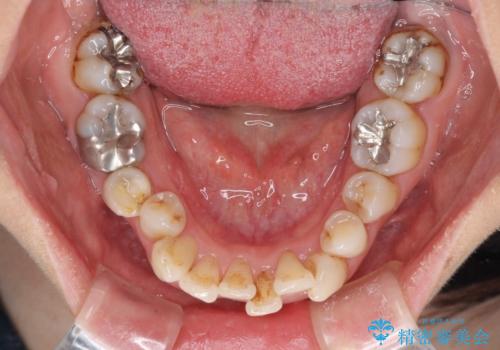

- 前歯の歯並びやむし歯治療の跡、奥歯の銀歯を気にして来院された患者様です。

インビザラインによる矯正治療の後に虫歯や銀歯をセラミックにて補綴することとしました。